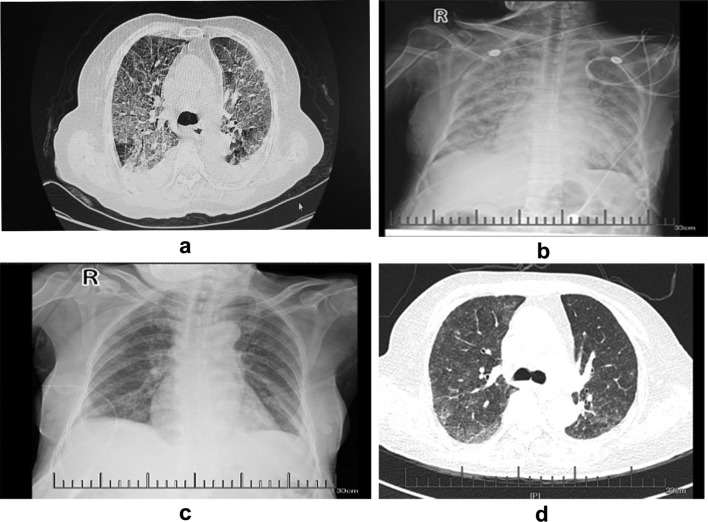

However, on the 34th day, she presented with aggravated dry cough and dyspnea and was subsequently admitted to a local hospital. A chest CT showed diffusing bilateral increased ground-glass opacity and reticulation and a medium amount of pleural effusion (Fig. 1a). A diagnosis of pneumonia and severe respiratory failure was made. Non-invasive positive pressure ventilation (NIPPV) and empirical antibiotics with meropenem and vancomycin were administered, but her progressive dyspnea and severe hypoxemia worsened. She was then transferred to our hospital. Her heart rate was 127 beats/min (bpm), and her respiratory rate was 32 breaths/min. Pulse oximetry revealed hypoxemia and 90% oxyhemoglobin saturation. The oxygen index (OI) value was 82.5, her leukocyte count was 13.2 × 109/L, and her procalcitonin level was 2.28 ng/mL; no definite pathological microorganism was found in either the sputum or blood cultures. Troponin and pro-brain-type natriuretic peptide levels and echocardiography results were normal. A chest X-ray showed diffusing bilateral ground-glass opacity (Fig. 1b).

a On the 34th day following crizotinib treatment, the CT showed diffusing bilateral increased ground-glass opacity and reticulation. b Chest X-ray showing diffused bilateral ground-glass opacity. c Chest X-ray showing diffused bilateral ground-glass opacity after treatment with methylprednisolone and bevacizumab. d Chest CT scans showing that the diffuse lesions of both lungs were improved and the pleural effusion decreased significantly.

Although we were unable to evaluate the patient through bronchoscopy and lung biopsy because of her severe respiratory failure, a diagnosis of crizotinib-induced ILD, pneumonia, and type I respiratory failure was considered. The patient and her family members refused invasion ventilation. Crizotinib was discontinued, and NIPPV was supported with an inspired oxygen fraction (FiO2) of 80%. Treatment with 40 mg of methylprednisolone twice a day was initiated. However, the patient still had severe dyspnea. Then, 200 mg of bevacizumab was administered once a day on the second and fourth days, and her conditions gradually improved. There was a decrease in ground-glass opacity after treatment with methylprednisolone and bevacizumab, as shown by a chest X-ray (Fig. 1c).

Methylprednisolone was tapered to 32 mg daily and then reduced to 4 mg/d per week. As a second-line therapy, anlotinib was given orally five days later, once daily (8 mg) on days 1 to 7, which was increased to 12 mg daily on days 7 to 14 of a 21-day cycle. Chest CT scans showed that the diffuse lesions of both lungs were significantly absorbed, and the pleural effusion was significantly reduced seven days after anlotinib treatment (Fig. 1d).